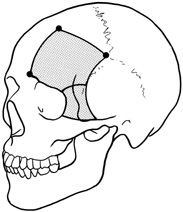

by Maroon and Kennerdell9 and Housepian.20 This operation has been termed the panoramic orbitotomy by Rootman21 because of the wide area of exposure offered by this procedure.  Fig. 13. Schematic diagram for transcranial orbitotomy in which the supraorbital

rim is removed en bloc with the frontal bone flap. This provides extensive

exposure to the superior and lateral orbit. Fig. 13. Schematic diagram for transcranial orbitotomy in which the supraorbital

rim is removed en bloc with the frontal bone flap. This provides extensive

exposure to the superior and lateral orbit.